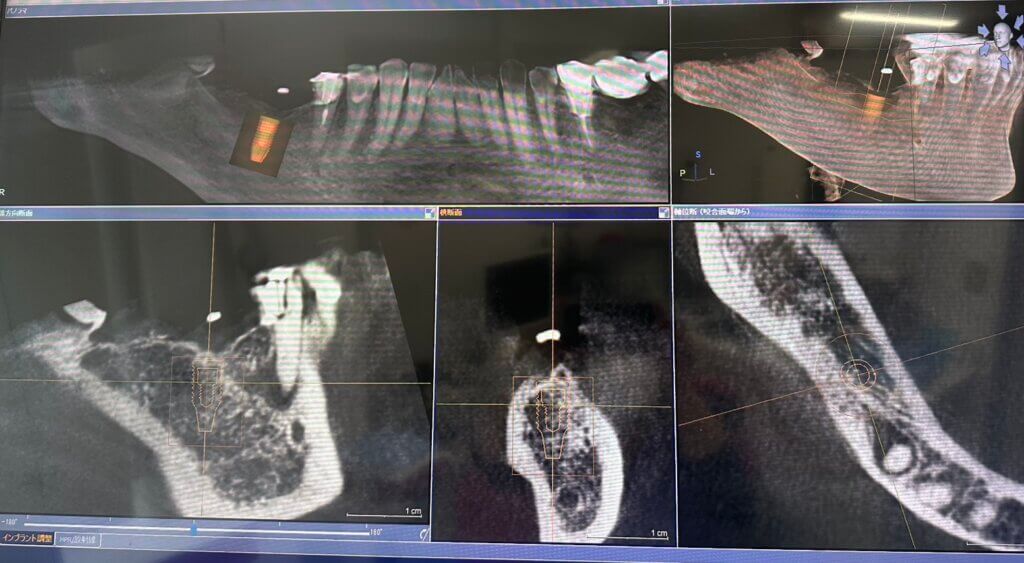

CTは通常のレントゲンでは見えにくい骨の厚みや神経の位置などを立体的に把握できる機器です!

主にインプラント治療などの高い精度が求められる治療の際に撮影しております。

被ばく量も抑えられているため、安心して撮影を受けていただけます。

このようにCTを撮影すると院長がササットインプラントの設計をおこなってくれます✊